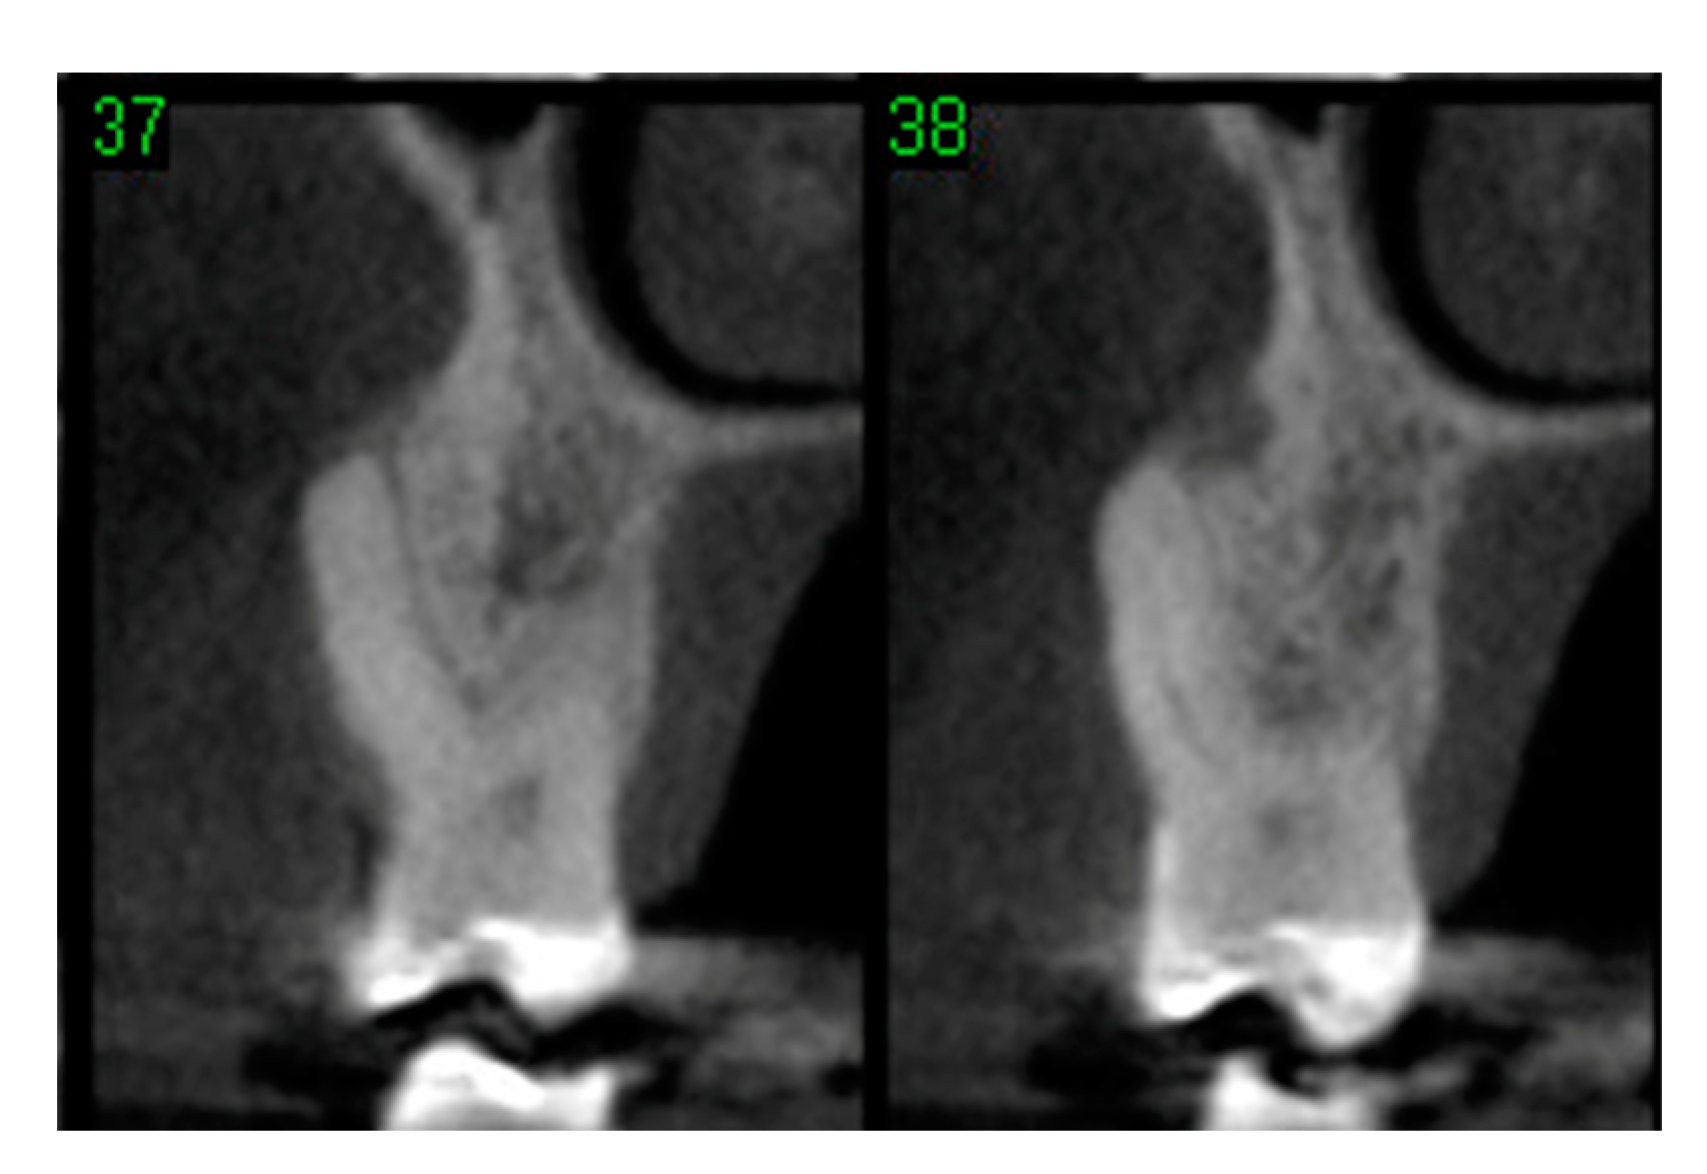

- Bleyan, S.; Gaspar, J.; Huwais, S.; Schwimer, C.; Mazor, Z.; Mendes, J.J.; Neiva, R. Molar Septum Expansion with Osseodensification for Immediate Implant Placement, Retrospective Multicenter Study with Up-to-5-Year Follow-Up, Introducing a New Molar Socket Classification. J. Funct. Biomater. 2021, 4, 66. [Google Scholar] [CrossRef] [PubMed]